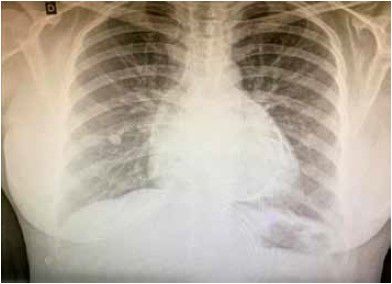

Paciente do sexo feminino, 43 anos, procura o pronto-socorro com queixa de dor torácica há 1 semana, do tipo pontada, retroesternal, sem irradiação e de caráter progressivo e contínuo, evoluindo com dispneia aos esforços há 2 dias. Sem comorbidades prévias e sem uso de medicações contínuas. Realizou a radiografia de tórax a seguir.

Durante a investigação clínica, qual alteração ecocardiográfica será encontrada no diagnóstico?

Ao exame físico, qual sinal clínico pode ser encontrado diante da suspeita clínica?